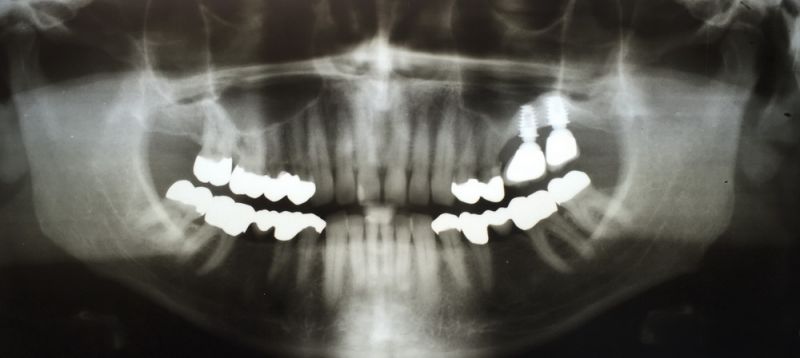

Patient aus Uelzen zum Recall

11347

Auch bei diesem Patienten gibt es wenig zu berichten. Die Versorgung befindet sich seit 1992, als inzwischen 24 Jahren, im Munde des Patienten.